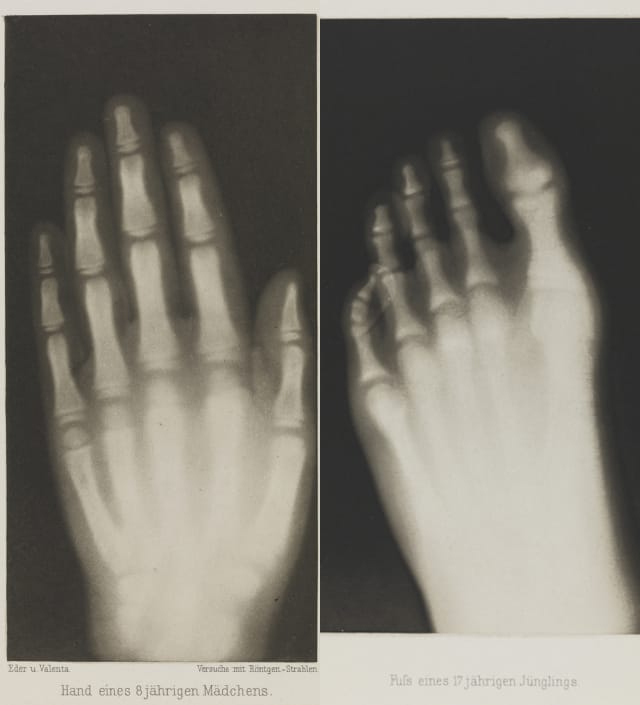

The National Media Museum in Bradford, England, holds a portfolio of Josef Maria Eder and Eduard Valenta’s 15 images for their 1896 publication Versuche über Photographie mittelst der Röntgen’schen Strahlen, which has recently undergone conservation and will go on display next year. The text that goes along with the images is fairly straightforward technical information on X-rays, which had been discovered just months before by Wilhelm Röntgen in late 1895, but the visuals are surprisingly elegant.

Eder and Valenta also included skeletal reveals from beneath the human skin, using photogravures, a photo-mechanical process predating the daguerreotype that uses a copper plate printing process. Eder had already been a leader in intensely documenting photography’s technical history, and with fellow chemist Valenta they used the photogravure combined with the X-ray to capture the interiors of a lizard with a winding tail, a rat with its ears still barely visible, a foot with a crooked toe, and even inanimate objects like leather and rocks.

As Ann Thomas wrote in Beauty of Another Order: Photography in Science: “Composed with simple factuality and a brilliant luminosity, they show just how exquisitely the stark graphic contrast of black, grey, and white typical of X-ray photographs could be translated in the delicate linear and tonal range of the photogravure process.” It might be easy to forget, but viewing these detailed photographs is likely the first time most people had seen the living workings of the body, and they do so beautifully, and with an obvious curiosity about suddenly being able to see what was previously invisible.